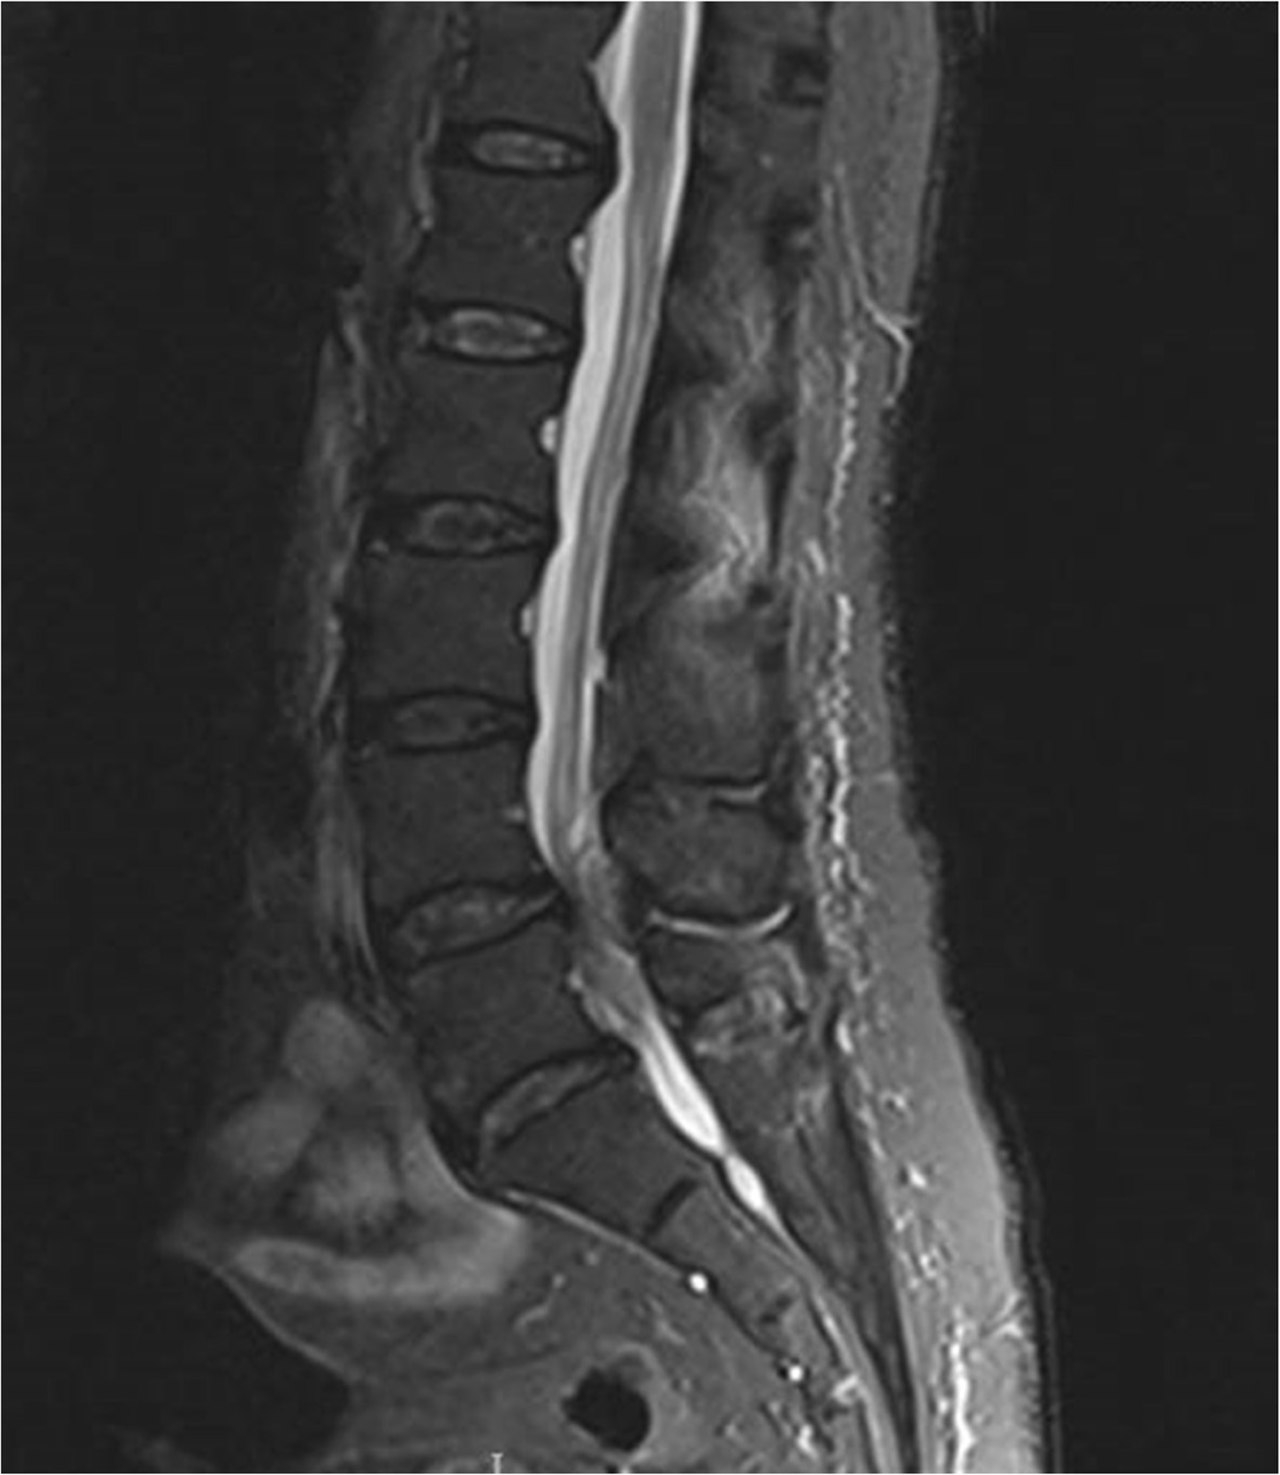

• Las lesiones de la columna lumbar pueden dañar el cono medular, la cauda equina o ambos. El síndrome de cola de caballo es la compresión de las raíces nerviosas por debajo de la terminación de la médula espinal. La disfunción de la raíz nerviosa se debe a la compresión directa de las estructuras circundantes. Las causas importantes incluyen trauma agudo; enfermedad ósea degenerativa crónica con retropulsión de fragmentos en el canal espinal; enfermedad del disco lumbar; infecciones como abscesos; tumor intraespinal y meníngeo; y hematoma intraespinal. Este síndrome puede ser una complicación rara de los procedimientos espinales menores y mayores. El síndrome de cauda equina generalmente se desarrolla como un proceso crónico insidioso a menos que se deba a un traumatismo agudo. Los síntomas pueden incluir dolor de espalda, dolor en las piernas, debilidad y calambres en las piernas. Los síntomas sensoriales pueden ser pérdida sensorial (anestesia en silla de montar) y dolor neuropático. La alteración del esfínter es común, especialmente con la progresión.

• La resonancia magnética es el método de diagnóstico por imágenes preferido.